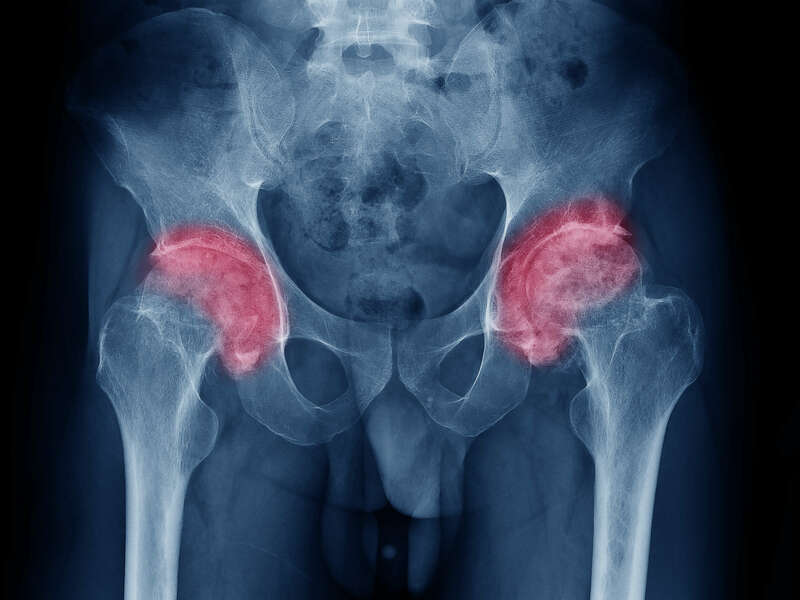

L’arthrose désigne un processus d’usure du cartilage liée au vieillissement. Ce n’est pas une fatalité liée à l’âge. Elle cause des dommages irréversible du cartilage qui perd au fur et à mesure son rôle de surface de glissement et d’amortisseur. La pression sur l’os s’accroît à mesure que l’épaisseur cartilagineuse diminue. Des excroissances osseuses, appelées ostéophytes, des kystes osseux et des ulcérations cartilagineuses se forment progressivement.

En réponse, la membrane synoviale devient inflammatoire et produit un liquide synovial. L’excès de pression articulaire et l’inflammation sont les causent des douleurs de hanche. La perte de congruence de l’articulation entraîne quant à elle, une diminution de la mobilité articulaire.

Elle sera confirmée par des examens radiologiques tels que des radiographies de hanche. En cas de doute diagnostic, afin d’éliminer un éventuel diagnostic différentiel, un scanner et/ou une IRM pourront être prescrits.